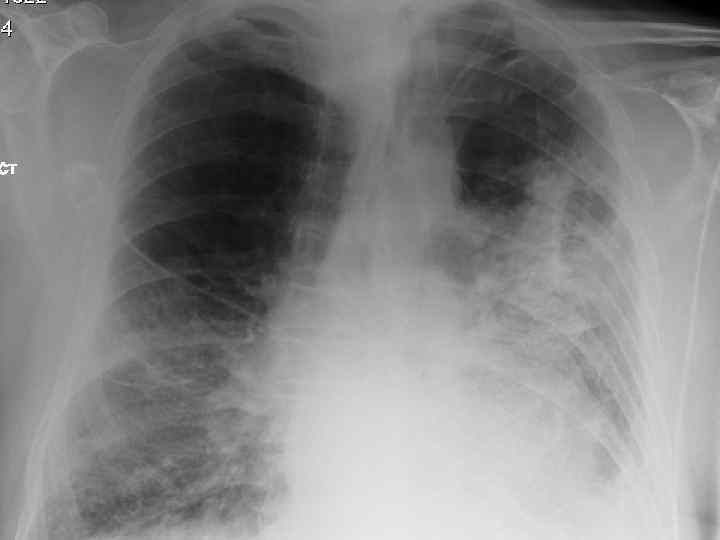

History n Mr X is a 74 year old Caucasian male n PC: Acute SOB n HPC: SOB episode began at 10 -11 am this morning gradually worsening, but suddenly became acutely worse. Noticed by neighbour. Ambulance blue lighted to AE resus

Examination n n n Anxious, gasping for breath, holding arms on trolley, Abdominal muscles used for breathing Central cyanosis Pulse 106 bmp regular HS I + II + 0 Apex beat laterally displaced Pitting right ankle oedema No sacral oedema

Respiratory R n n n L Resp rate 22 pm Trachea central Uneven lung expansion Hyperinflated upper chest Hyperresonant percussion Exp wheezing Insp crackles

Impressions n Pneumothorax n COPD/Fibrosing alveolitis n AHA n Congestive heart failure n Newly diagnosed Diabetes mellitus

Investigations. n CXR n CT n Arterial blood gases

Clinical features n Progressive breathlessness n Cyanosis n Pulmonary hypertension/cor pulmonale n Clubbing n Bilateral fine end insp. Crackles n X-ray shows ground glass appearance

Investigations n Chest X-ray n High res. CT scan n Respiratory function tests n Blood gasses n ANF, RF, ESR n Bronchoalveolar lavage n Biopsy